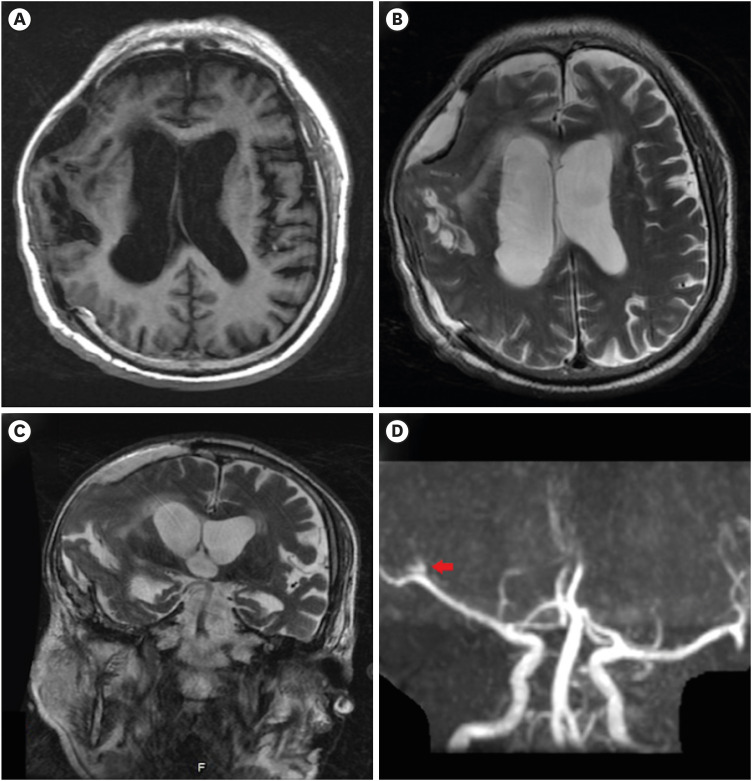

创伤后脑积水(PTH)是减压颅骨切除术后常见的并发症,通常表现为头痛、恶心、呕吐和乳头水肿等症状。在硬膜下血肿清除术后接受开颅手术的 PTH 患者中,颅外疝伴偏瘫是一种罕见的并发症。我们报告了一例在颅骨减压切除术后一个月内出现颅外疝的 PTH 患者。植入脑室腹腔分流术后,随着左侧大脑中动脉血流的恢复,左侧偏瘫得到明显改善,这在连续影像学检查中显而易见。临床医生在处理脑外伤患者时,血管损伤往往被颅内压增高所掩盖。精细的神经学和放射学检查以及及时的早期干预可为接受颅骨减压切除术的患者带来最佳治疗效果。

Post-traumatic hydrocephalus (PTH) is a commonly encountered complication following decompressive craniectomy, and is usually characterized by symptoms including headache, nausea, vomiting, and papilledema. Extracranial herniation accompanied by hemiplegia is a rare complication in patients with PTH who underwent craniectomy after subdural hematoma removal. We report a case of PTH that presented with extracranial herniation within one month of decompressive craniectomy. Following ventriculoperitoneal shunt implantation, left hemiplegia improved dramatically with restoration of the left middle cerebral artery blood flow, which was evident on serial imaging. Vascular compromise is often overshadowed by increased intracranial pressure when clinicians are dealing with traumatic brain injury patients. Delicate neurological and radiological examinations and prompt early interventions could lead to optimal outcomes in patients receiving decompressive craniectomy.